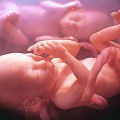

Mang thai chị em sinh đôi suốt 40 năm trong bụng

1439983657-8 Bào thai em sinh đôi đã thành hình chết lưu suốt hơn 40 năm mà người chị không hề hay biết. Cô Jenny Kavanagh, 45 tuổi, bà mẹ hai con đang sinh sống ở Twickeham (Anh) đã biết được